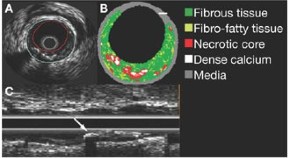

Coronary allograft vasculopathy is a severe complication of heart transplantation. In this paper, the authors used virtual histology intravascular ultrasound to characterize plaque burden and tissue composition over time in vessels of heart transplant recipients. Knowledge of the relationship between changes in plaque composition and clinical outcome might facilitate identification of high-risk patients who require more aggressive medical therapy.